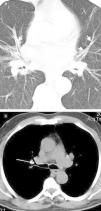

Central peribronchial soft tissue thickening (Fig. 2) was found in 37 (63.8%) cases. It occurred predominantly on the right side [right upper lobe (RUL), n=14; left upper lobe (LUL), n=9; right middle lobe (RML), n=23; lingula, n=7; right lower lobe (RLL), n=19; left lower lobe (LLL), n=10]. Intraparenchymal peribronchial cuffing (Fig. 3a) was seen in 36 (62%) patients with a proclivity to occur on the right side (RUL, n=12; LUL, n=11; RML, n=24; lingula, n=14; RLL, n=27; LLL, n=18). Central peribronchial soft tissue thickening and intraparenchymal peribronchial cuffing were most common in RML and RLL bronchi, respectively.

A 64-year-old male with cough and dyspnea. (a) CT image at the level of main pulmonary artery shows the central peribronchial soft tissue thickening (arrow) and narrowing of RUL bronchus. Also noted is the enlargement of main pulmonary artery (double head arrow). (b) Chest CT with lung window reveals the collapse of RML (star) as well as RLL peribronchial soft tissue thickening (arrow) with obliteration of the apical segmental bronchus of the right lower lobe.

Bronchial narrowing and obstruction were found in 37 (63.8%) and 11 (19%) patients, respectively. Multiple bronchial stenoses occurred in 23 (39.7%) patients (two bronchi, n=12; three bronchi, n=9; five bronchi, n=2). Bronchial stenosis was more prevalent in the right lobes compared to their contralateral counterparts (RUL, n=16; LUL, n=6; RML, n=21; lingula, n=7; RLL, n=14; LLL, n=10).

Likewise, bronchial obstruction was more commonly seen on the right side (RUL, n=3; LUL, n=1; RML, n=7). No bronchial obstruction was detected in lingula, right, or left lower lobes. Interestingly, RML bronchus was most commonly affected by anthracofibrosis with either stenosis or obstruction.